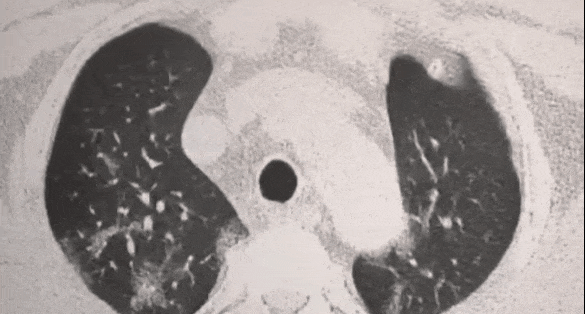

受损的肺细胞会形成肺结节,进而引发肺部纤维化、甚至肺ai

医学上对肺结节没有特效药,一般只能手术切除,对肺部的伤害大,有副作用。

没有清理肺部的自由基治标不治本,肺结节容易二次复发。

特别是年龄大的老年人,90%的肺细胞都被过剩自由基攻击过,肺部有很多结节,经常胸闷气短、咳嗽、呼吸不畅。

吸烟十几年了,去医院检查查出肺结节,经常咳嗽、哮喘,有时候胸闷得慌。

吃了2瓶,胸闷气短减少了,结节也变小了!

@湖北 谢女士:

之前体检肺窗示左肺下叶见微小结节灶,直径约3.0mm,吃了6瓶,肺结节已好转啦